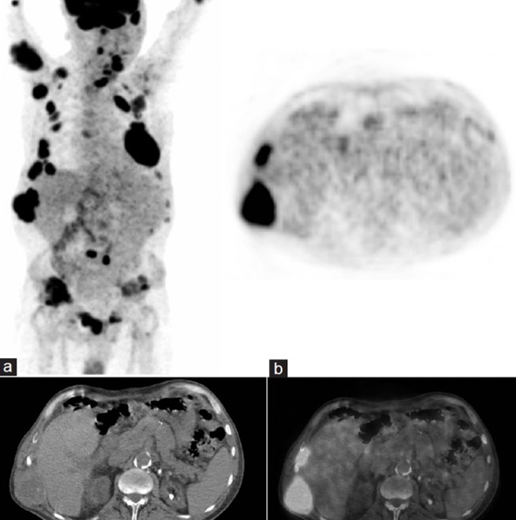

Рис. 7: ПЭТ/КТ и визуализация бурых опухолей при гиперпаратиреозе. Ограниченные данные свидетельствуют о высокой чувствительности, но низкой специфичности ПЭТ/КТ в диагностике бурых опухолей

Инструментальные проявления бурых опухолей имеют крайне неспецифический характер. Активное свечение на ПЭТ/КТ делает их похожими на метастатические опухолевые очаги, а литический характер поражения костей, прослеживаемый во многих случаях бурых опухолей, делает их похожими на миеломную болезнь. Это подтверждает целесообразность морфологической верификации бурой опухоли.

После гемипаратиреоидэктомии, а также при проведении медикаментозного лечения (цинкальцетом, золедроновой кислотой, препаратами витамина D) необходима динамическая оценка лабораторных показателей, отражающих метаболизм костной ткани, в частности, ПТГ, кальций крови (общий и ионизированный), щелочная фосфатаза, фосфаты. Допустимым методом оценки лечебного эффекта гемипаратиреоидэктомии является ПЭТ/КТ при доказанном отсутствии первичной опухоли, которая может быть источником костных метастазов и при условии проведённого ПЭТ/КТ – исследования перед началом лечения.